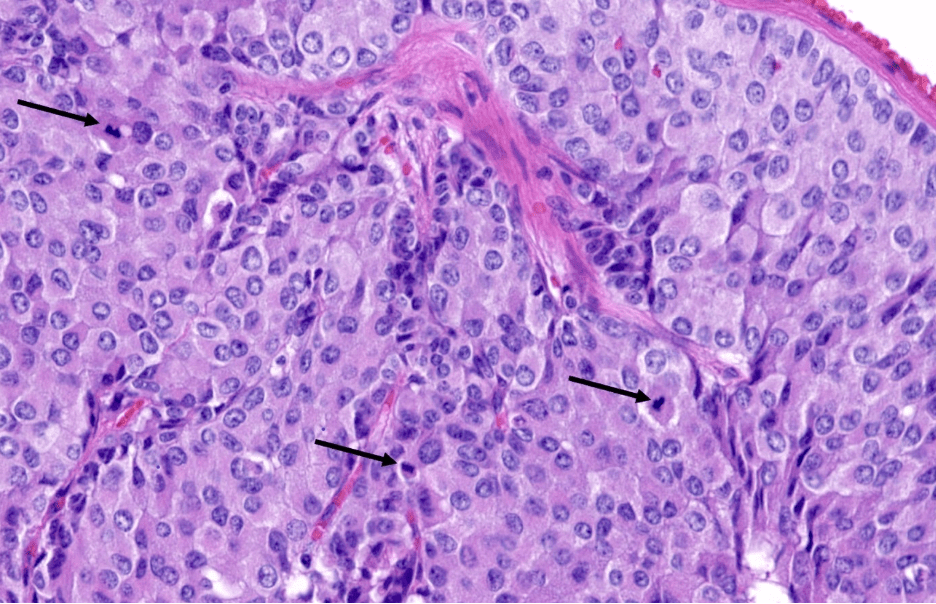

Name the coronary cusp indicated by the arrow

What is the right coronary cusp?